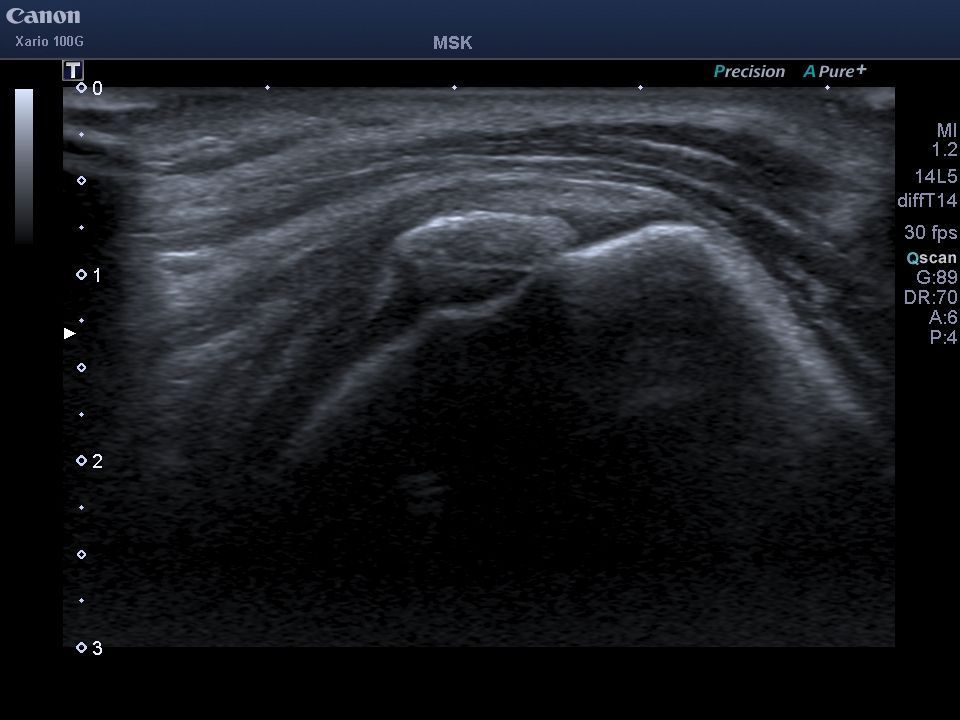

El Dr. López Velázquez es un médico especialista en rehabilitación con amplia experiencia en el tratamiento eficaz del dolor de hombro.

Realiza más de 10 técnicas diferentes, todas guiadas con imagen ecográfica, consiguiendo así una máxima eficacia para resolver problemas como:

- Rotura tendinosa parcial o total.

- Calcificaciones. Realizando lavado- aspiración de la calcificación (técnica también llamada barbotaje).

- Bursitis.